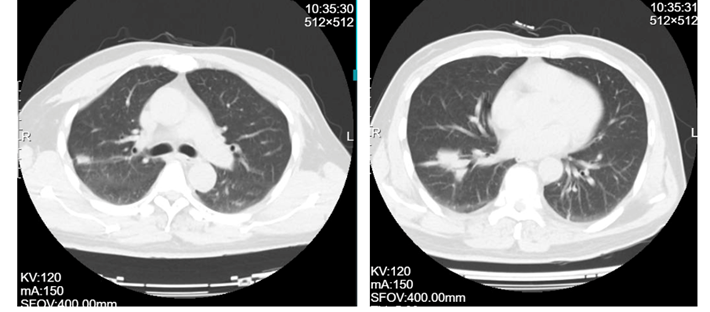

患者男性,74岁,退休在家,1月前无明显诱因突发上背部疼痛,起始为隐痛,后出现双下肢无力(肌力3级+),双下肢针刺感,走路踩棉花感。